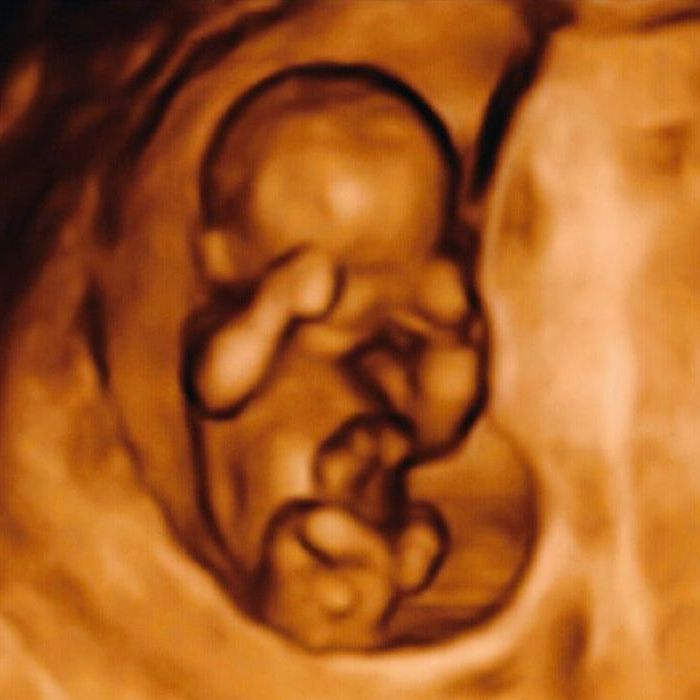

Ziel der NT-Messung ist die frühe und individuelle Abschätzung der Wahrscheinlichkeit des Down-Syndroms. Dazu wird durch eine spezielle Ultraschalluntersuchung in der 12. – 14. Schwangerschaftswoche der Nackenbereich des Feten vermessen und intensiv angeschaut.